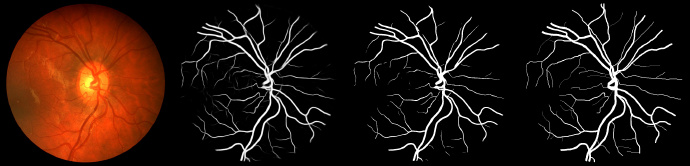

The original image, predicted probability image, predicted binary image and groundtruth

DRIVE: